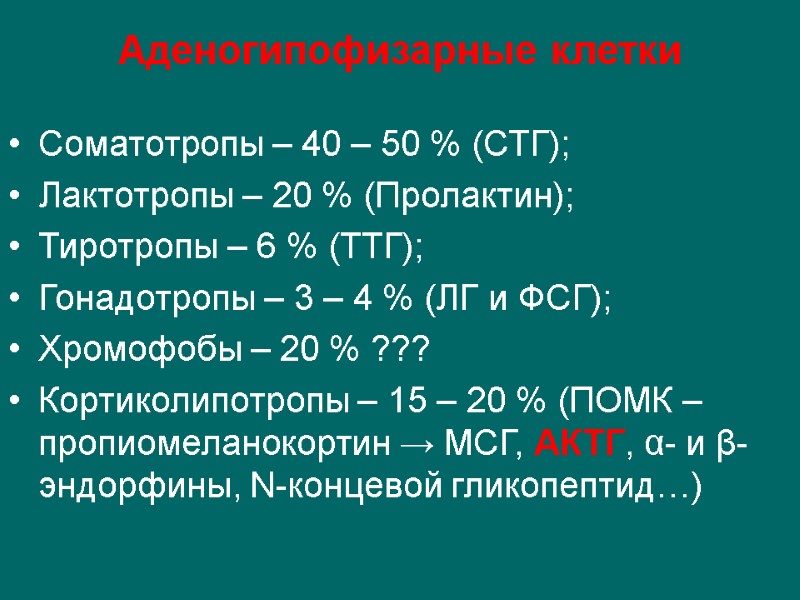

Аденогипофизарные клетки Соматотропы – 40 – 50 % (СТГ); Лактотропы – 20 % (Пролактин); Тиротропы – 6 % (ТТГ); Гонадотропы – 3 – 4 % (ЛГ и ФСГ); Хромофобы – 20 % ??? Кортиколипотропы – 15 – 20 % (ПОМК – пропиомеланокортин → МСГ, АКТГ, α- и β- эндорфины, N-концевой гликопептид…)